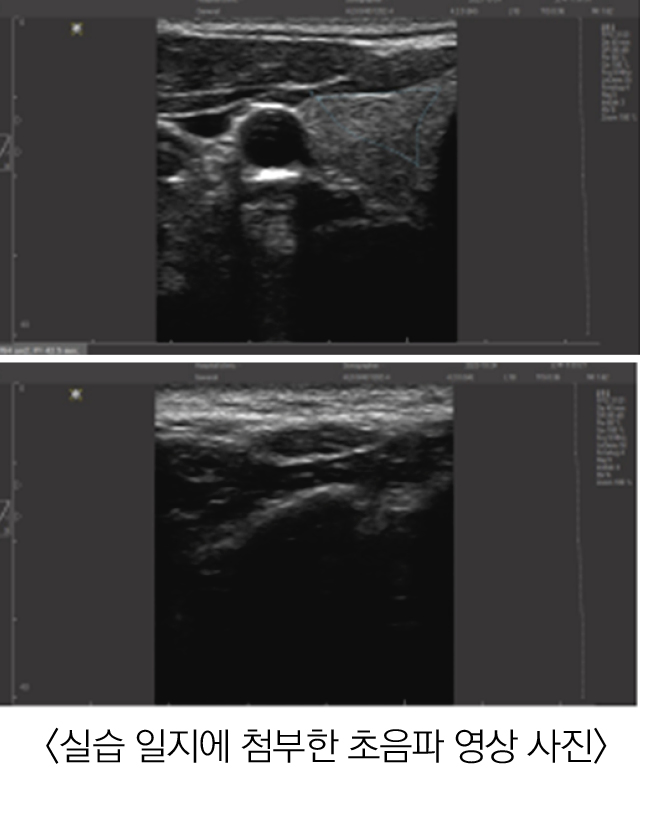

그런데 실습 시간에 교수님께서 초음파 영상을 통해 인체 구조물을 파악하는 것을 보니 사람마다 다른 인체 구조물을 초음파로 확인할 수 있겠다는 생각이 들었다.

초반에는 실습 전 교수님의 초음파 기기 사용을 관찰하고 영상 해석만 들었지만, 이후에는 교수님의 시범을 토대로 학생들이 직접 초음파를 사용할 수 있었다. 나는 흉복부 자침 실습에서 초음파를 처음 사용해 봤다. 흉복부에는 폐를 비롯한 장기들이 내부에 존재했기에, 시술자의 역할을 맡았던 나로서는 부담이 됐다.

그런데 자침 전 초음파 기기를 활용하니 폐와 내부 장기의 대략적인 위치를 파악할 수 있었을 뿐만 아니라 안전심도(안전범위)를 측정할 수 있었다. 덕분에 침을 놓는 나도, 침을 맞는 친구도 안심하고 실습에 참여할 수 있었다. 그 뒤로도 실습 시간에 초음파 기기를 활용해 인체 내의 주요 동맥, 장기를 관찰했고 이전에 학습한 인체 구조에 대한 이해를 넓힐 수 있었다.